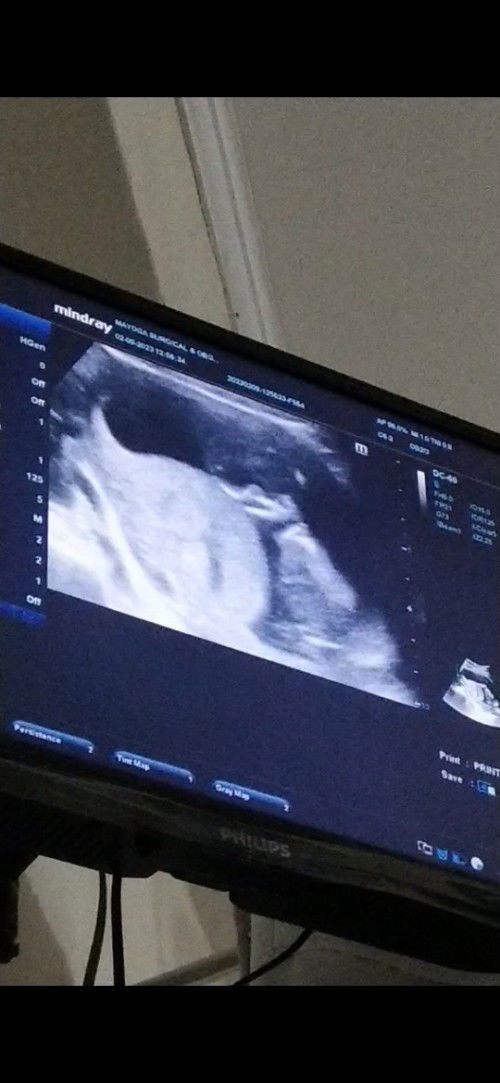

Tanong lang po with regards uterine muscle contraction at 16 weeks.

Hi po. Tanong lang po sana. I'm 16 weeks pregnant, panay travel with history of sub chorionic hemorrhage. Last scan ko po was 9 Feb 2023, may bump po sa uterus ko due to contraction daw po. Has anyone experienced this po? Thank you.